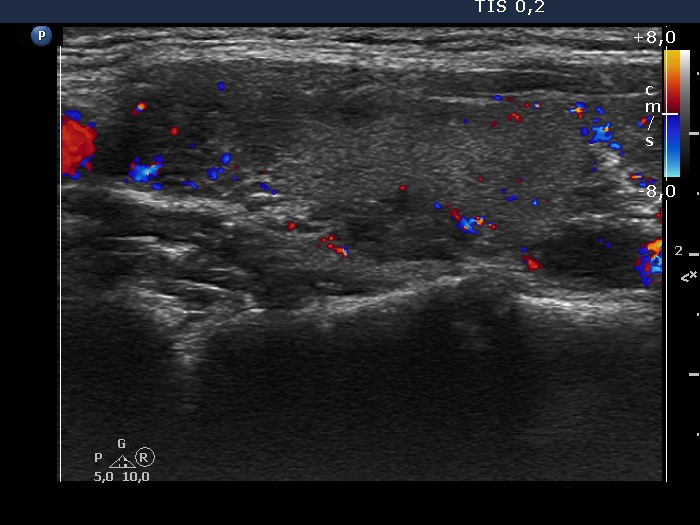

Discrete lesion or nodule in Hashimoto's thyroiditis - case 24 (430) (ultrasonographic picture 7)

Right lobe, longitudinal scan

Right lobe, longitudinal scan, color Doppler mode. The vascularization is not specific.